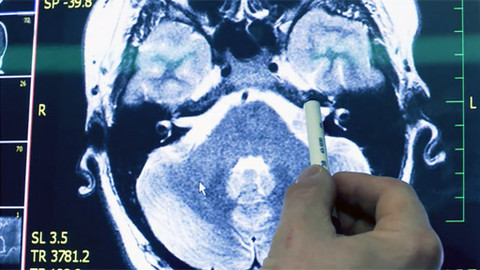

Operace velkého nádoru

Poslední vysílání 8. 11. 2012 na ČT2